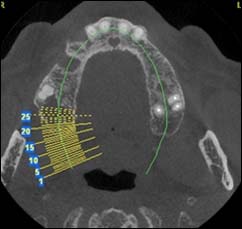

Dernière technologie à notre disposition, cette technique permet de voir en 3 dimensions des images de votre bouche et de mettre en évidence des pathologies ou des anomalies que les autres techniques ne permettent pas d'objectiver.

Coupe axiale